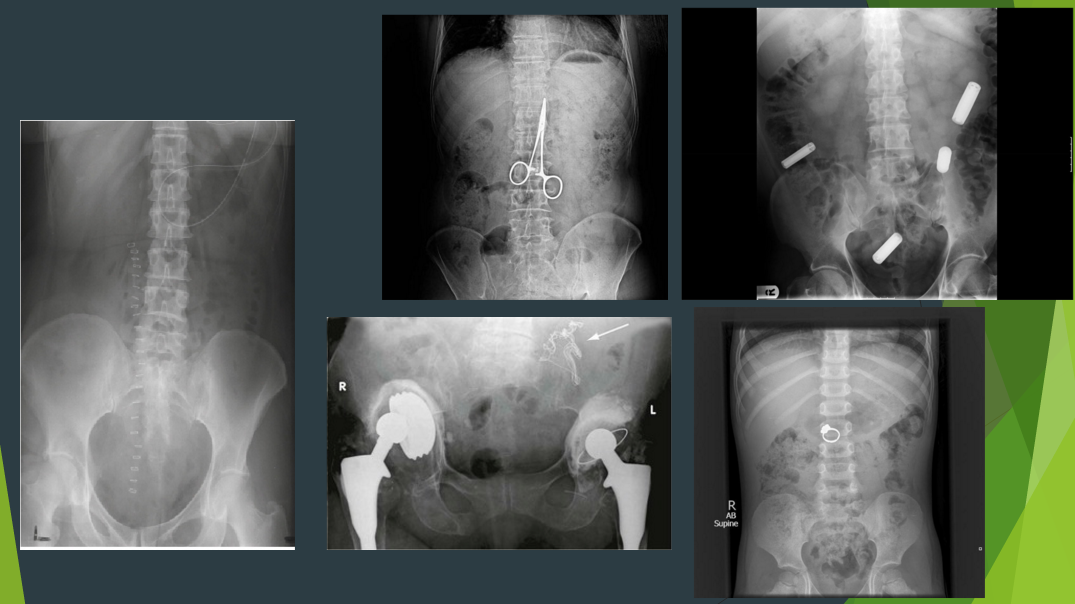

What are these xrays showing

1?

2?

Find the Foreign Body!